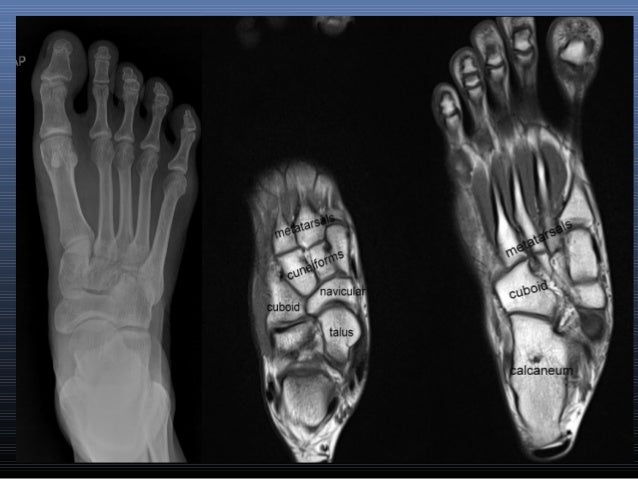

Foot Muscles Mri - Magnetic resonance imaging (MRI) image showing foot ... / The aim of this study is to describe clinical and mri patterns of …. Foot muscles mri / normal magnetic resonance imaging anatomy of the ankle. The traditional full body mri can cost up to $3,500 limiting patients who need the imaging to get a full and proper diagnosis. Your doctor, with the help of a radiologist, can then examine these images to determine whether there is anything wrong with your foot or ankle. Magnetic resonance (mr) imaging has opened new horizons in the diagnosis and treatment of many musculoskeletal diseases of the ankle and foot. Magnetic resonance images of the foot may be digitized to quantify muscle architecture.

LOWER LIMB | Radiology Key from radiologykey.com Magnetic resonance (mr) imaging has opened new horizons in the diagnosis and treatment of many musculoskeletal diseases of the ankle and foot. However, the roles of the extrinsic foot muscles during running have not been adequately identified. Case contributed by dr andrew dixon. Mri is the choice of modality for further imaging the ankle and foot after obtaining initial radiographs. It demonstrates abnormalities in the bones and soft tissues before they become evident at other imaging modalities. Your doctor, with the help of a radiologist, can then examine these images to determine whether there is anything wrong with your foot or ankle. The majority of soft tissue lesions in the foot and ankle are benign. Magnetic resonance imaging (mri) is the modality of choice in diagnosing accessory muscles, delineating their relationship to adjacent structures, and differentiating them from soft tissue tumors.

Foot muscles mri / normal magnetic resonance imaging anatomy of the ankle. The purpose of this study was to investigate the relationship of muscle mri findings and gait all dm1 patients presenting with foot drop showed high intensity signals. Magnetic resonance imaging (mri) is the modality of choice in diagnosing accessory muscles, delineating their relationship to adjacent structures, and differentiating them from soft tissue tumors. Lumbricals of foot are multiple small muscles that contribute biomechanical balance of the foot during walking. The traditional full body mri can cost up to $3,500 limiting patients who need the imaging to get a full and proper diagnosis. Coronal images are perpendicular to the long axis of the metatarsals. Mri of the ankle and feet They are mainly responsible for assisting some of the extrinsic muscles in their actions. Human anatomy diagram from the back view. Anatomical structures of the ankle and foot and specific regions (major joints) are visible as dynamic labeled images. The intrinsic foot muscles comprise four layers of small muscles that have both their origin and insertion attachments within the foot foot muscles mri. This imaging technique assesses the ligaments and tendons, neurovascular structures (tarsal tunnel and plantar fascia), and the osseous structures(19). The muscles of the dorsum of the foot are a group of two muscles, which together represent the dorsal foot musculature.

They are named extensor digitorum brevis and extensor hallucis brevis. Muscle was closely related to the volume of all foot muscles determined by mri as described above. Magnetic resonance imaging, otherwise known as mri, uses a combination of magnetic fields and radio waves to take images of the internal structures of your body. Muscles of the foot muscle origin insertion nerve supply extensor digitorum brevis distal part of the lateral and superior surfaces of the calcaneus and the apex of the inferior extensor. Your doctor, with the help of a radiologist, can then examine these images to determine whether there is anything wrong with your foot or ankle. Top suggestions for plantar foot muscles mri. This ensures anyone who will benefit from an mri to fully heal their pain can have one at an affordable cost. Mri has surpassed nuclear medicine imaging due to the greater specificity of mri and its ability to delineate osseous anatomy as well as discrete abscesses and sinus tracts diagnostic of infection. The purpose of this study was to investigate the relationship of muscle mri findings and gait all dm1 patients presenting with foot drop showed high intensity signals. Involved early gray = muscle: The intrinsic foot muscles (ifm) are the main local. Magnetic resonance (mr) imaging has opened new horizons in the diagnosis and treatment of many musculoskeletal diseases of the ankle and foot. Near normal foot mri for reference.

Near normal foot mri for reference. It demonstrates abnormalities in the bones and soft tissues before they become evident at other imaging modalities. The muscles acting on the foot can be divided into two distinct groups; Anatomical structures of the ankle and foot and specific regions (major joints) are visible as dynamic labeled images. Your doctor, with the help of a radiologist, can then examine these images to determine whether there is anything wrong with your foot or ankle. At advanced foot and ankle centers of illinois, we have made this expensive imaging a lot more affordable. Coronal images are perpendicular to the long axis of the metatarsals. They are mainly responsible for assisting some of the extrinsic muscles in their actions. This ensures anyone who will benefit from an mri to fully heal their pain can have one at an affordable cost. 6 mri is commonly ordered in the diabetic patient to rule out infection in the presence of an ulcer, to evaluate the severity of charcot arthropathy. The aim of this review is to provide the reader with a comprehensive overview of the magnetic resonance imaging (mri) characteristics of the most common benign and malignant soft tissue neoplasms which occur around the foot and ankle. Those fibers of the most medial and largest belly are… The first purpose of this study was to estimate in vivo the volume and distribution of healthy plantar intrinsic foot muscles.